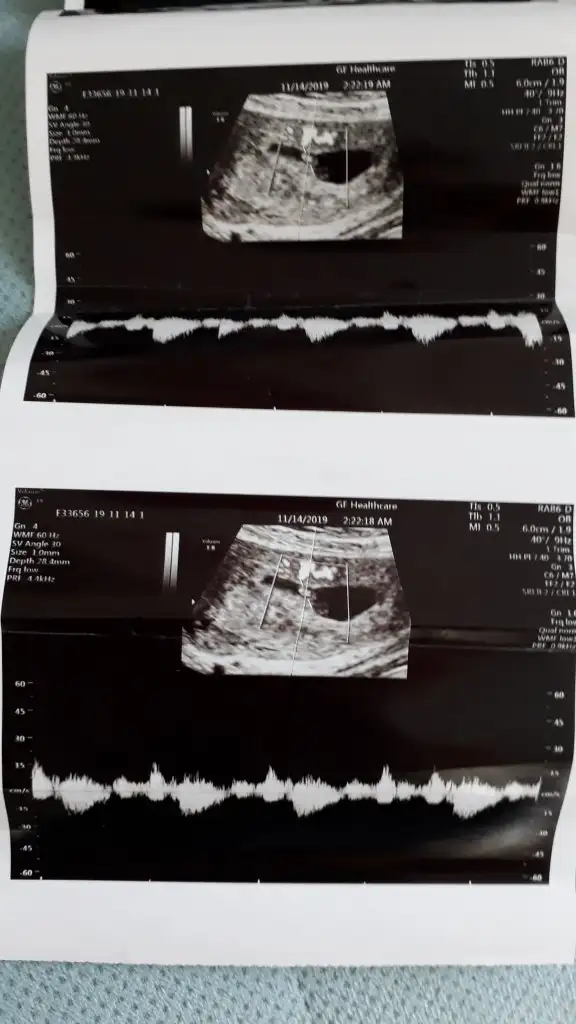

VajinalKarından bakıldıysa kız vajinalsa erkek

Kesem bi degisik. Karından ultrason 7 haftalik.

Karından bakıldıysa erkek vajinal ise kız 11 yada 12 hafta nub teorisine bakalımBen de yorum bekliyorum![]()

Onu hatırlamıyorum ama bu karından bunu da yorumlar mısınız? 6+3 görüntüsüKarından bakıldıysa erkek vajinal ise kız 11 yada 12 hafta nub teorisine bakalım![]()

Erkek buna göreOnu hatırlamıyorum ama bu karından bunu da yorumlar mısınız? 6+3 görüntüsü

6 haftalık sagda ise erkek kese konumu için 5+ ve 6+ olmalı en dogrusu 11 yada 12 hafta nub teorisi diyorum6 haftalıkken karından usgde sağda 8 haftalıkken karından usgde solda